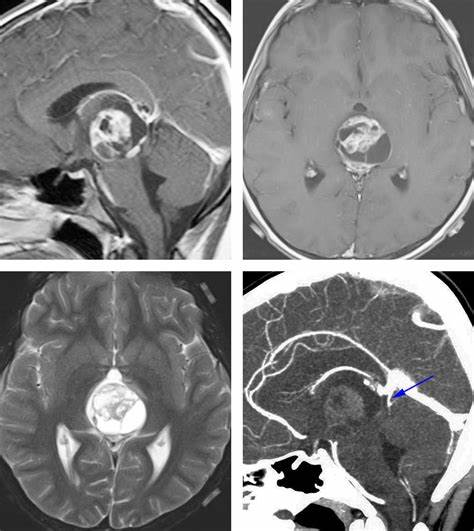

松果体位于间脑的顶上方,主要分泌褪黑素,其作用与脑垂体的黑色素细胞刺激素相反,使两栖类皮肤色素变浅。松果体是神经内分泌的转换器,起生物钟的作用。 松果体区脑瘤 约占...

松果体肿瘤代表了具有挑战性的外科病变,本文强调完全显微外科切除术(CMR)在松果体区域肿瘤中获得良好长期效果的作用...